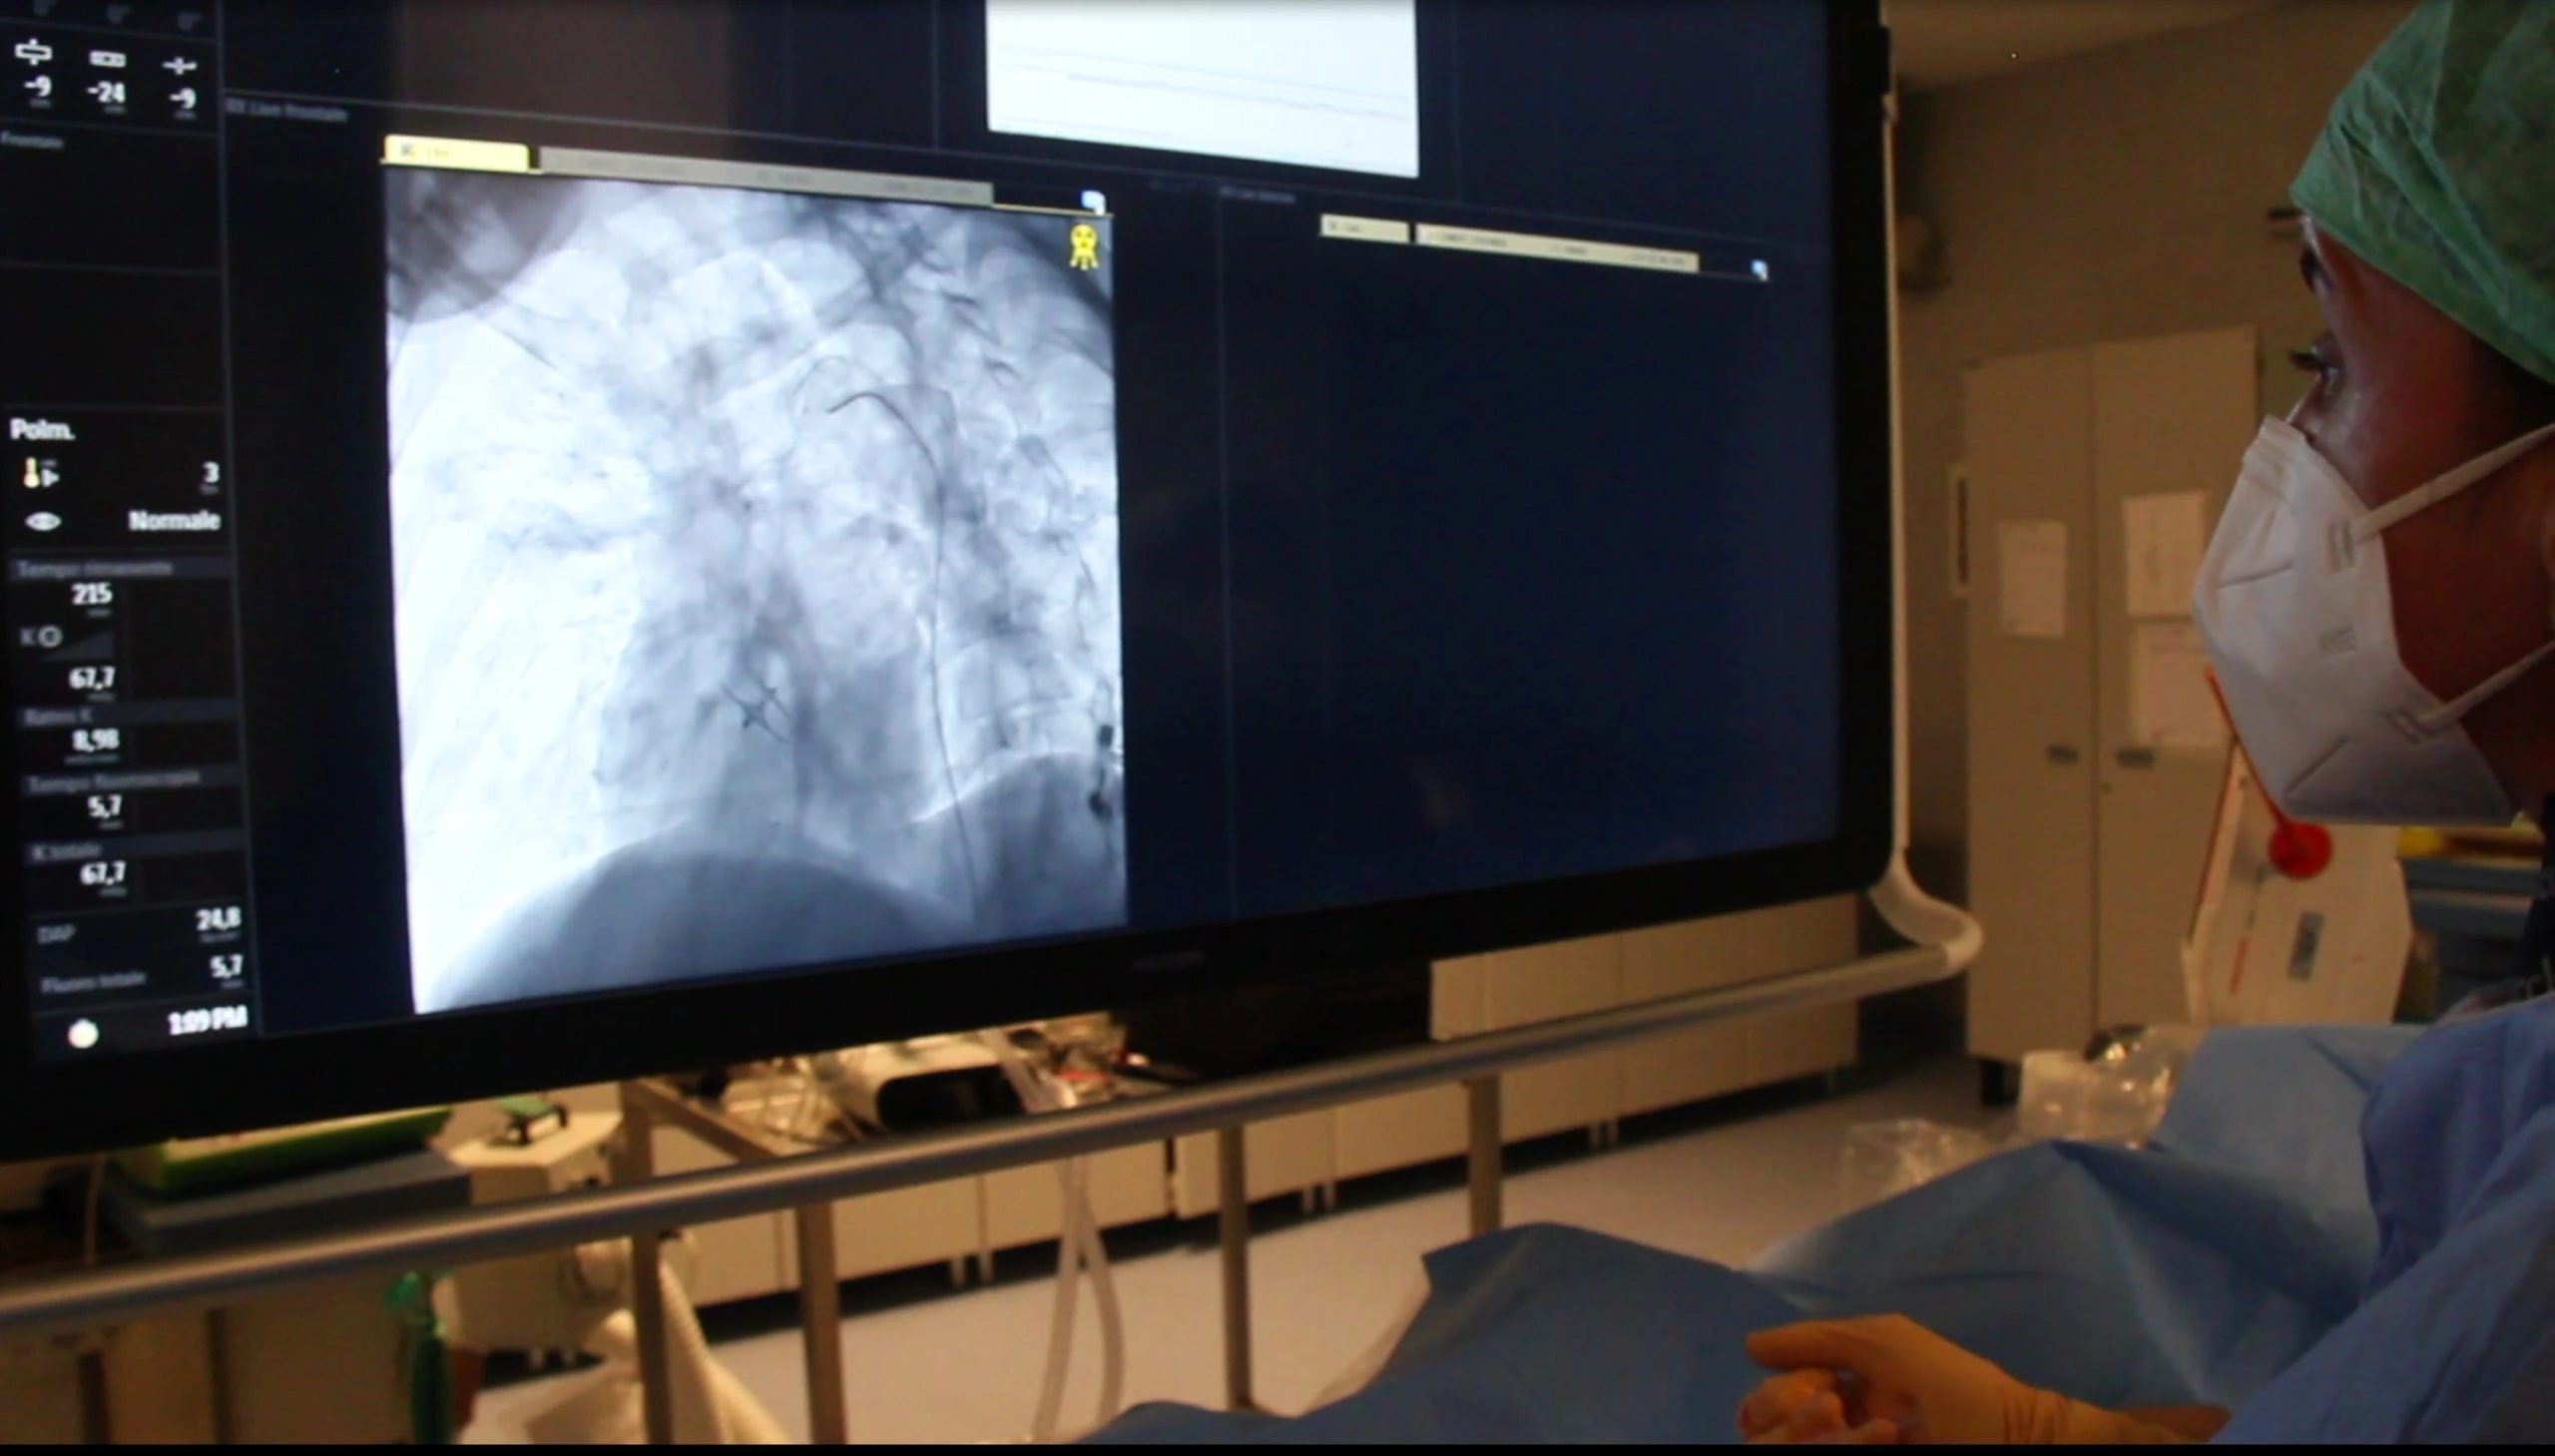

Procedura

L’embolizzazione consiste nell’introdurre da un accesso arterioso periferico (arteria

femorale, arteria omerale, arteria radiale) un sottile catetere. Per fare questo si fa

Il catetere viene spinto attraverso i vasi fino alla zona patologica da trattare. Si

spingono poi attraverso il catetere stesso dei materiali vari (come apposite “spirali”

oppure “particelle” o liquidi come delle colle, polimeri, etc) che chiudono i vasi.